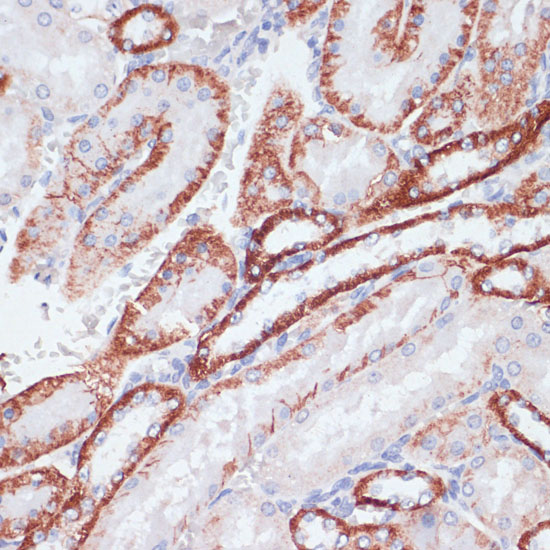

DescriptionTFRC Polyclonal Antibody. Unconjugated. Raised in: Rabbit.

ApplicationWB, IHC, IF, IP